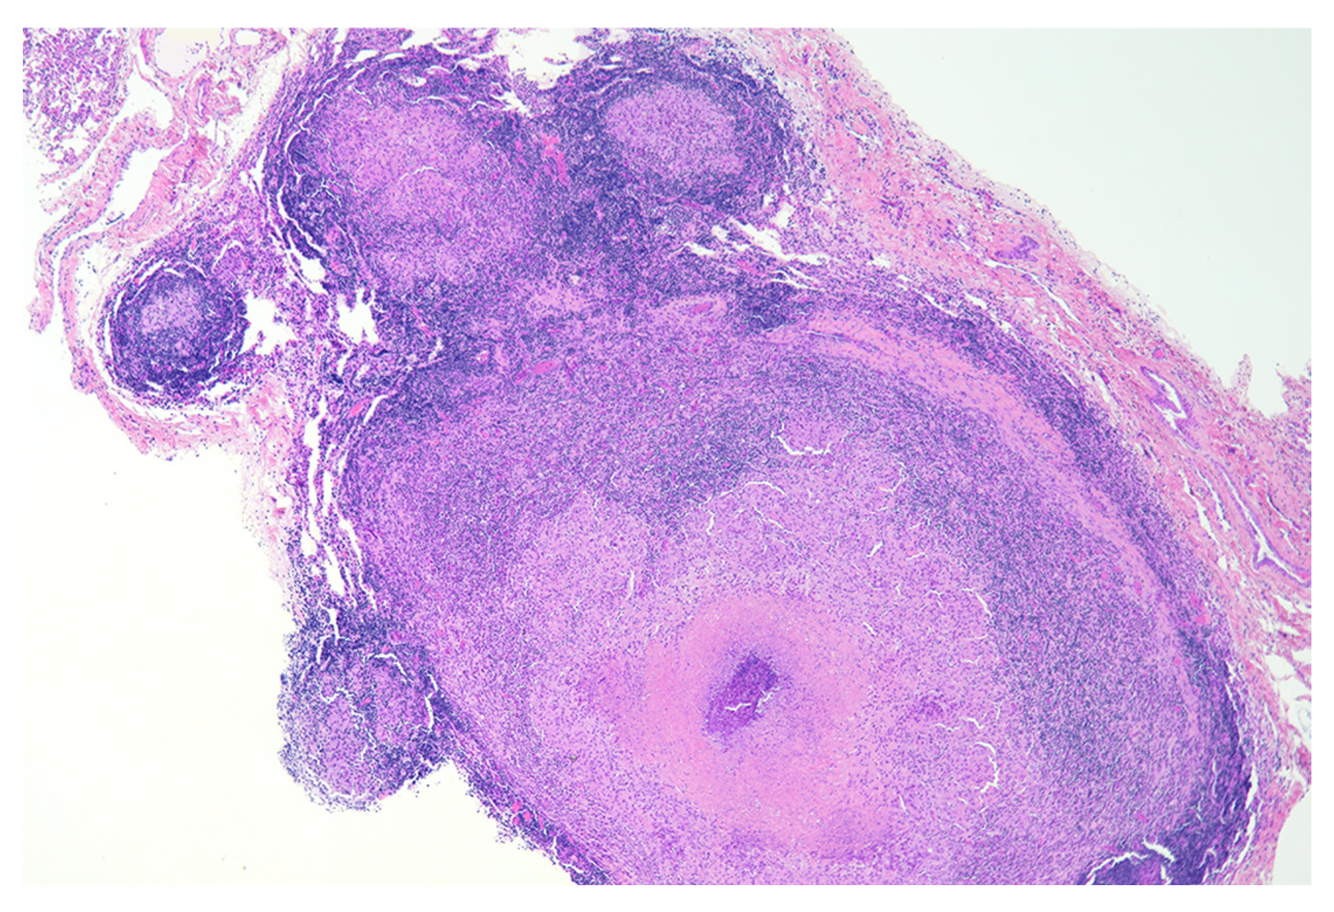

What structure is shown here? Which disease could it be associated with? What type of hypersensitivity is this?

A

Granuloma

Bovine TB

Type IV